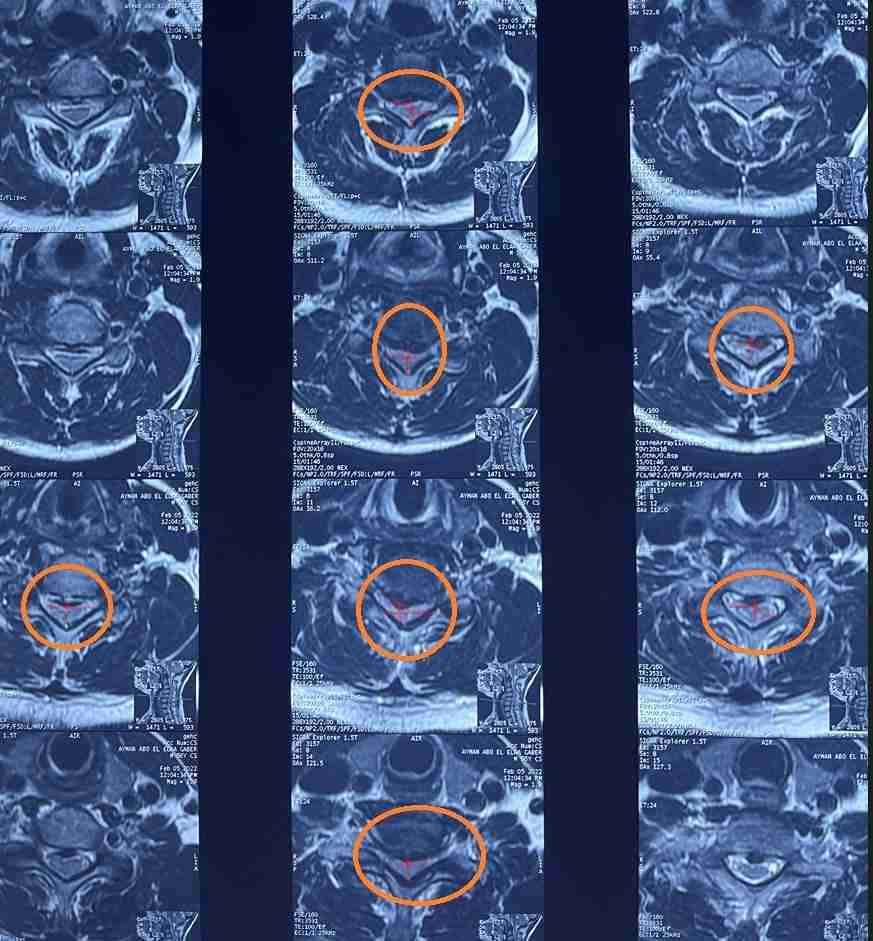

مريض 55 عام يعاني من ضعف بالجانب الأيمن بالجسم وخذل بالأطراف الأربعة مع تيبس اثناء الحركة ناتج عن اصابته بضيق شديد بالفقرات العنقية مع تحدب للأمام بالفقرات العنقية. تم علاجه عن طريق اجراء جراحة لتوسيع مجري القناة العصبية العنقية وتركيب نظام تثبيت خلفي لإصلاح التحدب وتثبيت الفقرات العنقية. كما هو واضح من صور اشعة الرنين قبل الجراحة وصور النخاع بعد رفع الضغط عنه ووضع نظام التثبيت وصور الاشعة المقطعية بعد المتابعة.

تم إجراء جراحة ناجحة للتوسيع الخلفي وتثبيت الفقرات العنقية. هذا الإجراء المتخصص يهدف إلى علاج الضغط على الحبل الشوكي في منطقة الرقبة، والذي ينتج عن تضيق القناة الشوكية أو عدم استقرار الفقرات العنقية.